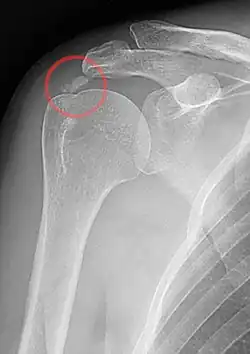

An x-ray showing calcific deposits in the area of the tendons of the rotator cuff muscles

Calcific tendinitis is typically diagnosed by physical examination and X-ray imaging.[1] During the formative phase, X-ray images typically reveal calcium deposits with uniform density and a clear margin.[1] In the more painful resorptive phase, deposits instead appear cloudy and with unclear margins.[1] By arthroscopy, formative stage deposits appear crystalline and chalk-like, while resorptive stage deposits appear smooth resembling toothpaste.[1] Ultrasound is also used to locate and assess calcium deposits. In the formative stage, deposits are hyperechoic and arc-shaped; in the resorptive stage deposits are less echogenic and appear fragmented.[1][3]